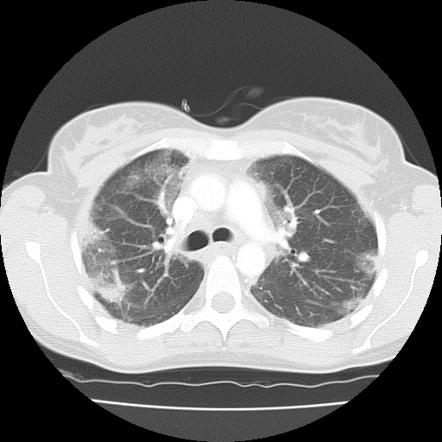

اما چه اتفاقی در ریه می افتد که می تواند نمای ggo در سی تی اسکن ریه را برای شما بسازد؟

این نکته بسیار مهم است چون در تشخیص و درمان به شما کمک بسیار مهمی خواهد کرد .این که بدانید چه بلایی سر ریه و بافت آن آمده که نمای ground-glass opacity (GGO) در سی تی اسکن ریه بیمار دیده می شود.

بریم با هم و این دلایل را به اختصار بدانیم:

دلایل به وجود آمدن ggo در سی تی اسکن ریه :

اولین دلیل incomplete pulmonary aeration هست: یعنی آلوئول ها نصف و نیمه از هوا پر هستند یا یکی پره و یکی خالی! یعنی ممکنه نصف هوا باشه و نصف مایع .یا اینکه بیمار خوب نفس نتونسته بکشه .

دومین دلیل به وجود آمدن ggo در سی تی اسکن ریه interstitial thickning هست: یعنی اینترستیشیوم ضخیم شده و به خاطر فیزیک سی تی اسکن و تضعیف بیشتر اشعه میشه یک ggo در سی تی اسکن ریه دید! نکته به شدت مهمیه چرا؟ چون خود این ضخیم شدگی باعث میشه آلوئول ها خوب باز نشن و مورد اول اتفاق بیفته

اما سومین عامل که باعث ایجاد یک ggo در سی تی اسکن ریه میشه اینه که بر اثر بیماری های مختلف آلوئول ها نصف و نیمه و یا به صورت رندومی پر از خون، چرک ، اگزودا و… باشه .